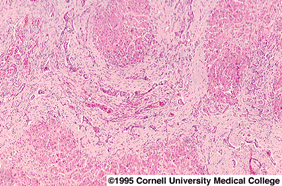

As mentioned in my welcome page, I taught a course on the biology of addiction, in which I went into exquisite detail about alcohol and other psychoactive drugs and their short- and long-term effects on the body. In the chapter dealing with alcohol, I included images of photomicrographs taken of a healthy liver, a fatty liver, and a liver showing cirrhosis. I used these images in the textbook I wrote, Men, Women, and Their Addictions: A Biological Approach (2003).

The tissue inside a healthy liver is divided into blocks called sinusoids, in which blood vessels course between the sinusoids to allow the rapid movement of blood to the liver for delivery of digested foods which will be ultimately distributed to the rest of the body, and of drug compounds, each of which will undergo a chemical detoxification process. To me, a photomicrograph of a healthy liver resembles an aerial view of a well-planned city subdivision, in which the blocks (sinosoids) are clearly separated by streets (blood vessels).

If the individual continues to drink, the cells of the liver will die, and the tissues which formed the sinusoids will appear crushed, with no blood vessels coursing between them, and this is indicative of cirrhosis: